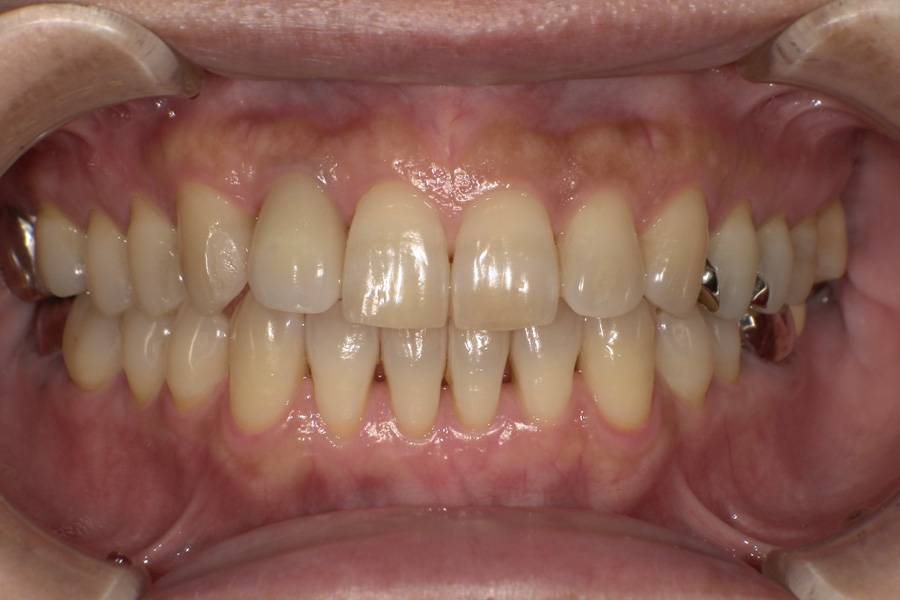

生涯、美味しく食べられる

豊かな人生を

“健口づくり”からサポートする

正しい診査診断、的確な治療をすることで、

歯だけでなく全身の健康に繋がります。

虫歯があるから削ったり悪くなったから抜くのではなく、まずは虫歯と歯周病が起きないようにより良い環境づくりをすること、そうすることによって歯を長く維持することが可能となります。

そのためには、健康状態に関する情報と生活習慣などの状況を把握したうえで、お口の中のリスク評価をおこないます。

その結果をもとに、お一人お一人にあった治療計画をご提案させていただきます。

ご自分の歯で食べ、話し、笑える幸せを生涯にわたり維持するためのお手伝いを全力でさせていただきます。